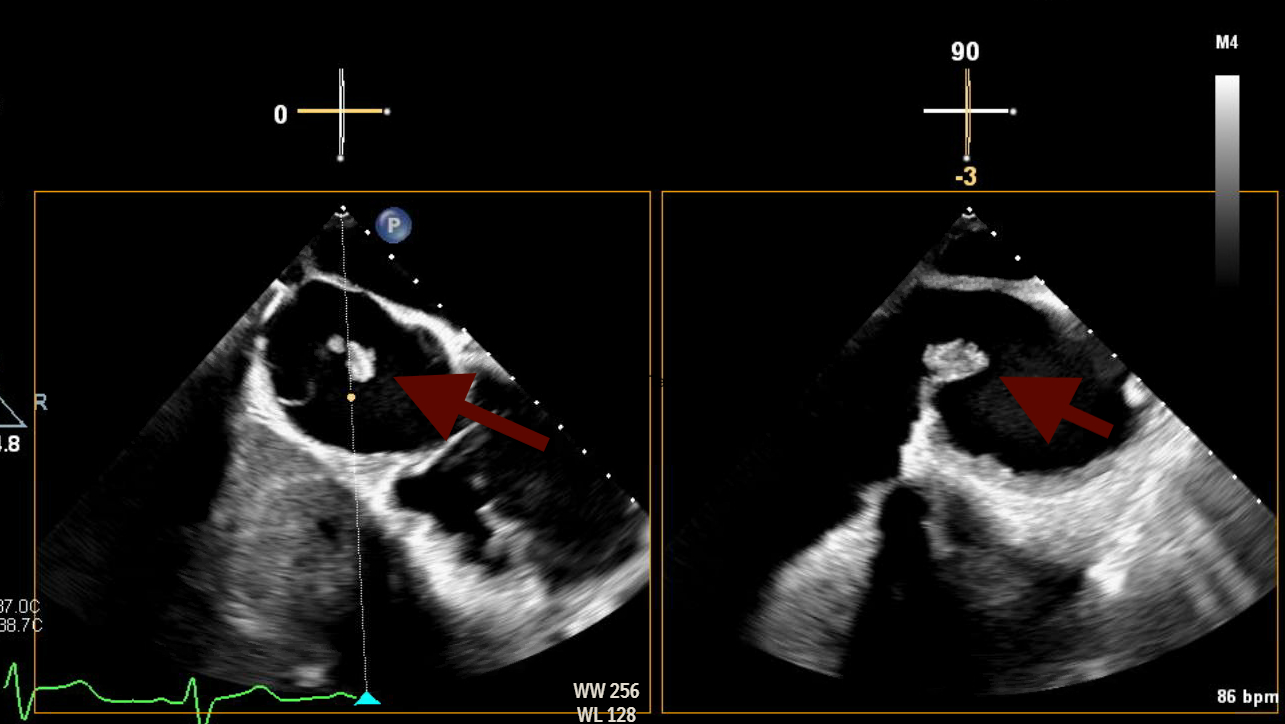

Abstract Body (Do not enter title and authors here): Here is a rare and diagnostically challenging case of infective endocarditis (IE) involving the Chiari network in a 47-year-old female with a complex cardiac and social history. She had a history of intravenous drug use (IVDU), prior methicillin-sensitive Staphylococcus aureus (MSSA) bacteremia involving the mitral valve (MV), and methicillin-resistant Staphylococcus aureus (MRSA) endocarditis requiring tricuspid valve (TV) replacement with a CorMatrix bioprosthesis. She presented with a 3-day history of fever, progressive right groin pain and swelling, and worsening dyspnea. On admission, she was afebrile but hypotensive and had tachycardia. On examination, she had a loud holosystolic murmur in the left lower sternal border, a pulsatile right groin mass with a bruit, alongside multiple healed track marks on her lower extremities. Blood work was notable for leukocytosis. Computed tomography of the chest, abdomen, and pelvis revealed multiple pulmonary septic emboli and a right femoral artery pseudoaneurysm with an arteriovenous fistula confirmed on duplex ultrasound. Transthoracic echocardiogram (TTE) showed preserved ejection fraction (60-65%), normal aortic and mitral valves, but poor visualization of the prosthetic tricuspid valve. Blood cultures grew MRSA, and the patient was started on IV vancomycin. Transesophageal echocardiogram (TEE) revealed a large, mobile echogenic mass attached to the Chiari network (CN), positioned in line with the tricuspid regurgitant jet. These new findings, absent on prior imaging, strongly suggested isolated Chiari network endocarditis (CNE)

Right-sided infective endocarditis (IE) is a rare clinical entity, accounting for less than 10% of all IE cases. Among these, involvement of the CN- the embryonic remnant of the right valve of the sinus venosus and present in under 2% of the population- is even rarer, with only a few reported cases to date. IVDU remains the leading risk factor for right-sided IE, as seen in our patient. The true incidence of CNE is likely underreported due to the limited sensitivity of TTE, which can make visualizing it challenging. TEE remains the imaging modality of choice for identifying such atypical presentations.

Our case reinforced the critical role of TEE in identifying uncommon, non-valvular sources of infection. In the absence of clear treatment guidelines and high surgical risk, the patient was treated conservatively with a 6-week course of antibiotics followed by repeat TEE for monitoring.